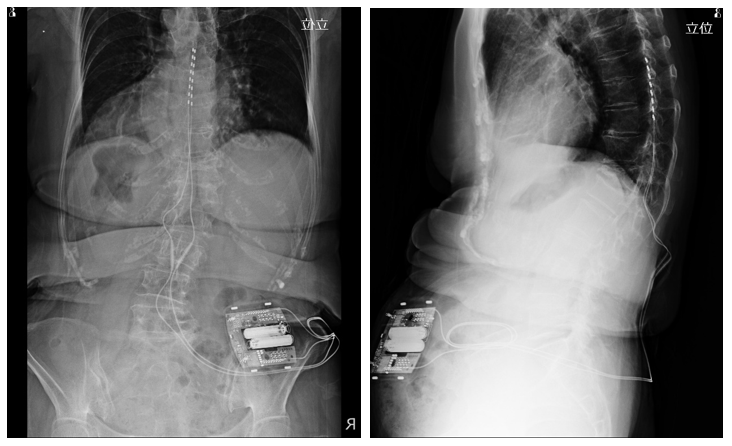

A 73-year-old woman with lumbar spinal canal stenosis presented with back pain, leg pain, and intermittent claudication. The skin color of her toes was grossly mispresent. A spinal cord stimulation therapy puncture trial was performed with the lead tip placed at the eighth thoracic vertebra. The surface body temperature of both lower extremities increased from 24.7℃ to 32.2℃ using a thermographic camera. NRS improved from 9 before treatment to 3 after treatment. The gross color tone and  edema of the toes also improved (Figures 2–4).

Figure 3 X-ray image after spinal cord stimulation therapy puncture trial.